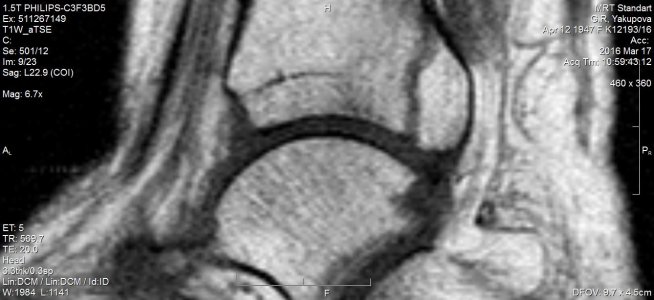

Недели 2 тому назад еще прошла МРТ, написали остеоартроз голеностопного сустава и стопы, минимального синовита голеностопного сустава, краевой косой перелом дорзальных отделов медиальной лодыжки. Что делать дальше? Врач не знает, так как своевременно не наложили гипс, прошло время. Помогите, пожалуйста, что мне делать, чтобы место перелома срослось? Наступать можно полностью на стопу или движение мешает сращиванию?это МРТ снимки